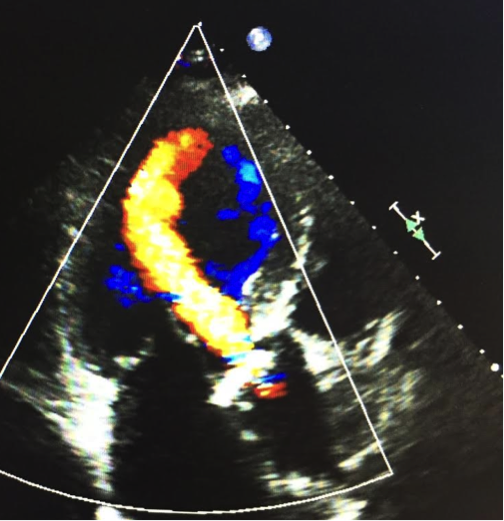

こちらは大動脈弁狭窄症と僧帽弁閉鎖不全症を合併している患者さんの心臓です。この画像からは、大動脈から左心室へと血液が逆流していることがわかります。

(提供:ニューハートワタナベ国際病院)